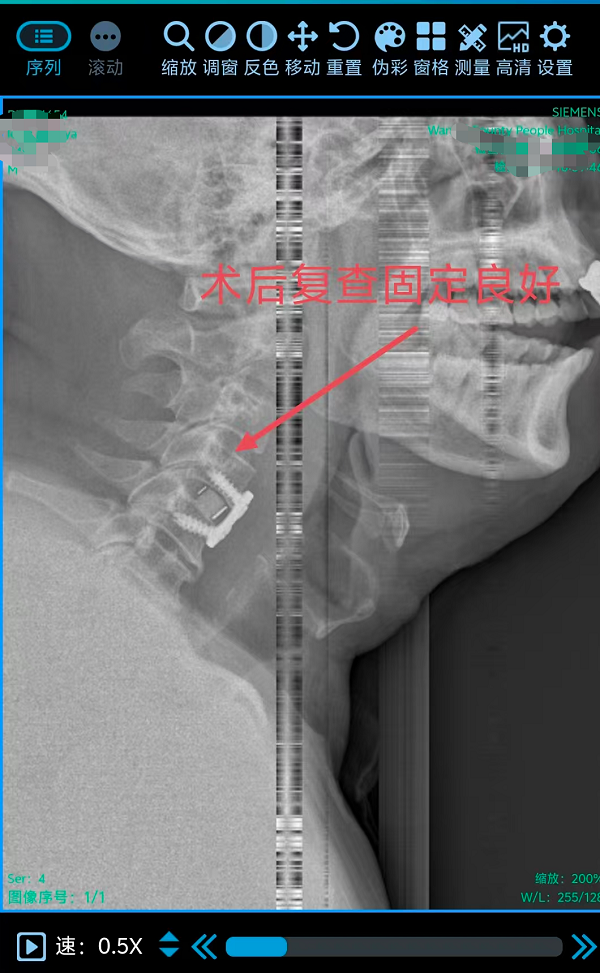

2. 为颈椎间盘巨大突出致肢体不全瘫患者行颈椎前路椎间盘切除融合内固定术(ACDF)(四级手术),该术式通过颈部前方的天然解剖间隙到达病变节段,在彻底解除脊髓和神经根压迫的同时,重建了颈椎的生理曲度和稳定性。手术团队凭借丰富的经验和精细的操作,在方寸之间精准完成了减压、植骨与内固定,有效避免了重要神经血管的损伤。